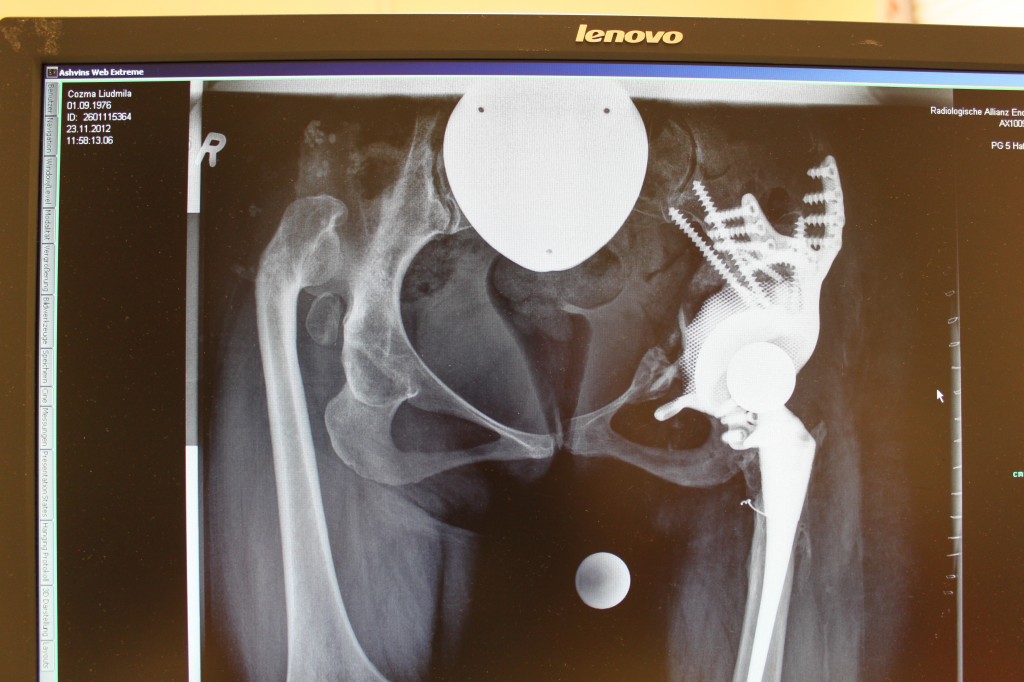

Röntgenbild des Hüftersatzes — анатомия тазобедренного сустава, фото и фотографииRöntgenbild des Hüftersatzes

Röntgenbild des Hüftersatzes

röntgenaufnahme des hüftgelenks. arzt wies im bereich des hüftgelenks, wo pathologie, wie z. б. bruch, zerstörung von gelenk, коксартроз, артроз erkannt wird. диагностика фон gelenkerkrankungen фон радиологии — анатомия тазобедренного сустава стоковые фото и фотографииRöntgenaufnahme des Hüftgelenks. Arzt wies im Bereich des Hüftgele